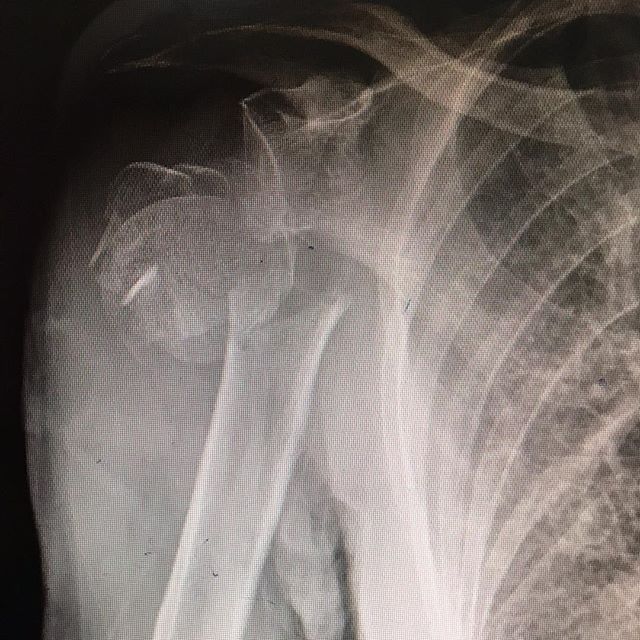

OMUZ CERRAHİSİ ve OMUZ HASTALIKLARI